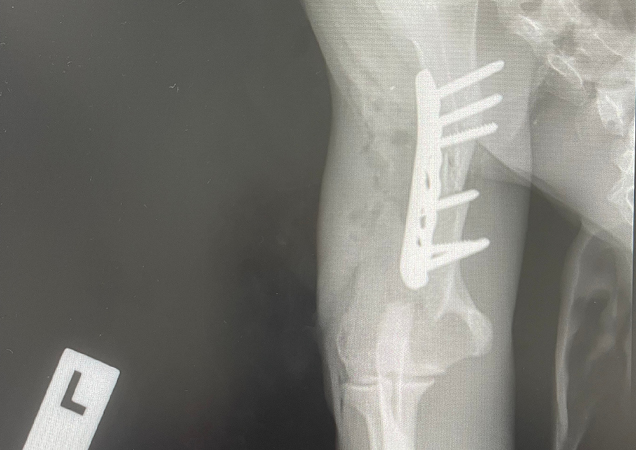

Thor suffered a fractured left humerus and abrasions to his body, with his injuries so severe, Veterinarian Dr Aiden Pickering was brought in to operate on him at the RSPCA Queensland Wildlife Hospital.